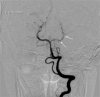

Arterial ischemic stroke is a rare but significant cause of neurological deficits in childhood. Even though there is a variety of risk factors, identifying the etiology can sometimes be a hard diagnostic challenge. Arteriopathies in general, and more specifically, arterial dissection is one of the uncommon pathologies that can cause incidents of pediatric stroke. We report a rare case of a young adolescent with posterior cerebral artery dissection after excessive consumption of caffeine, contained in energy drinks, only hours before the onset of neurological symptoms. A complete neuroimaging evaluation (MRI, intracranial US and digital subtraction angiography) at the admission and during the follow-ups supported the diagnosis of arterial dissection possibly caused by caffeine overconsumption.